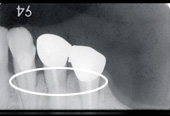

■症例写真

歯周病により溶けてしまった骨を再生造成し補正します。